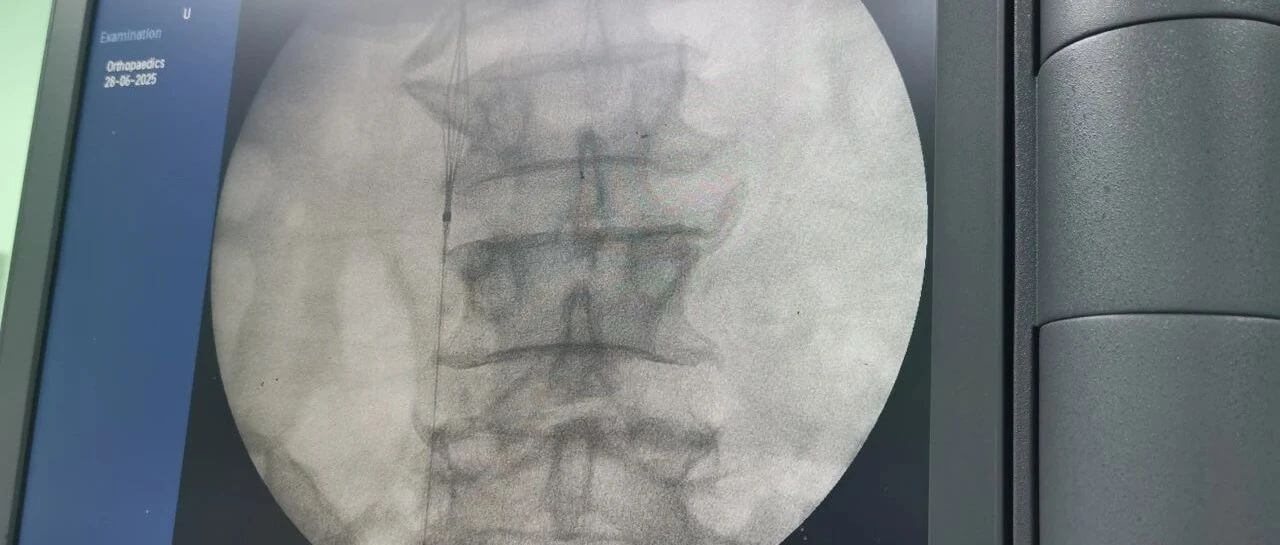

面對(duì)這一嚴(yán)峻挑戰(zhàn),羅軍副院長團(tuán)隊(duì)果斷決策,先行實(shí)施“下腔靜脈濾器植入術(shù)”。手術(shù)團(tuán)隊(duì)?wèi){借精湛的技術(shù),在患者的下腔靜脈(人體最大的靜脈干)內(nèi)精準(zhǔn)放置了一個(gè)特殊的“濾網(wǎng)”裝置——腔靜脈濾器。它的核心作用就是充當(dāng)“血栓攔截網(wǎng)”:

攔截脫落的血栓:有效捕捉從下肢深靜脈脫落的血栓碎片,防止其隨血流進(jìn)入心臟和肺部。

預(yù)防致命肺栓塞:從根本上大幅降低患者在骨折手術(shù)期間及術(shù)后康復(fù)階段發(fā)生肺栓塞的風(fēng)險(xiǎn)。

保障后續(xù)手術(shù)安全:為接下來必須進(jìn)行的、耗時(shí)較長的骨盆髖臼粉碎性骨折修復(fù)手術(shù)(尤其是利用3D打印技術(shù)進(jìn)行的精準(zhǔn)手術(shù))掃除了最大的安全隱患,提供了至關(guān)重要的手術(shù)安全保障期。